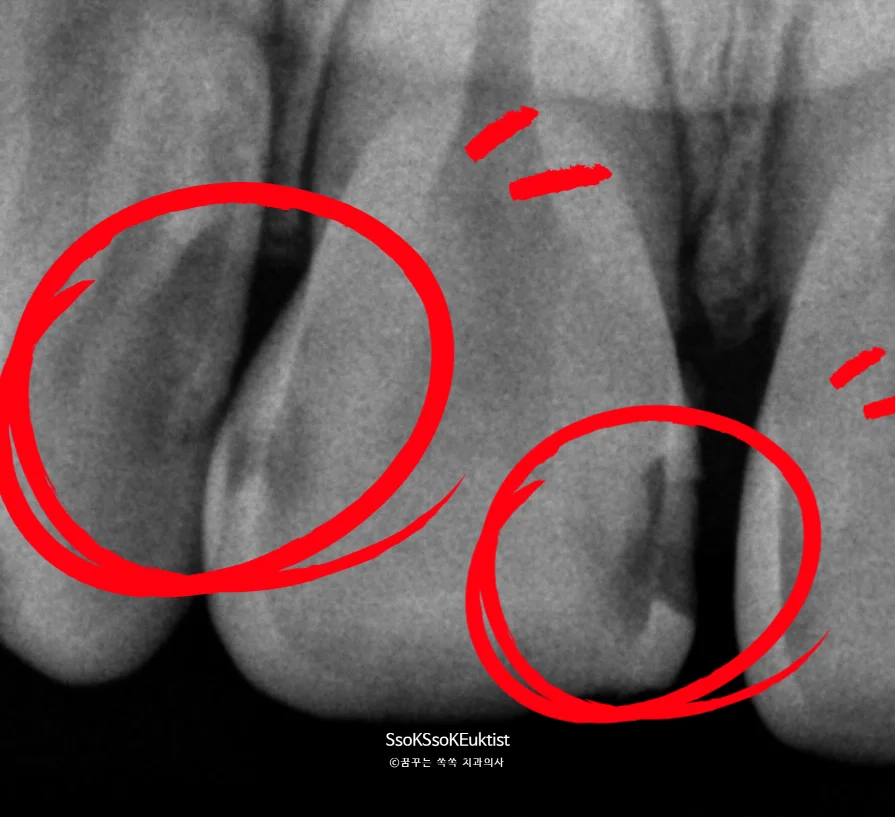

사진과 같이, 앞니 사이가 벌어져 있고 치아 끝부분이 깨져 있으며 오른쪽 중절치 안쪽·바깥쪽 충치, 오른쪽 측절치 안쪽에도 충치가 존재합니다.

이렇게 여러 문제가 한 번에 겹쳐 있으면 “라미네이트? 크라운?” 고민이 자연스럽게 생길 수밖에 없습니다.

하지만 반드시 큰 치료로 갈 필요는 없습니다. 정확한 조건만 맞는다면 ‘레진’으로 훨씬 보존적인 치료가 가능합니다.

- 충치가 신경까지 깊지 않을 것

- 치아 형태를 보존적으로 재건할 수 있을 것

- 삭제량을 최소화하고도 심미 회복이 가능할 것

이 모든 기준을 충족했기 때문에 레진 치료로 보존적이고 합리적인 치료가 가능합니다.^^